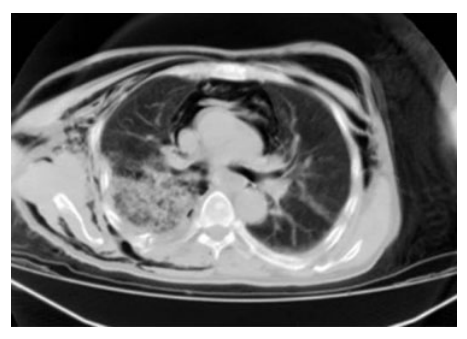

一名53岁的男性患者,因高处掉落的建筑材料砸中右肩和胸部区域而被送往急诊科。初步体检显示患者右肩部有表皮擦伤和广泛的皮下气肿,右前胸壁有一大约10×15 cm的连枷胸区域,并伴有呼吸困难。胸片显示右侧多根肋骨、锁骨和肩胛骨骨折,右侧液气胸以及广泛的皮下气肿(►图1和图2)。

图2. 患者胸部CT扫描。